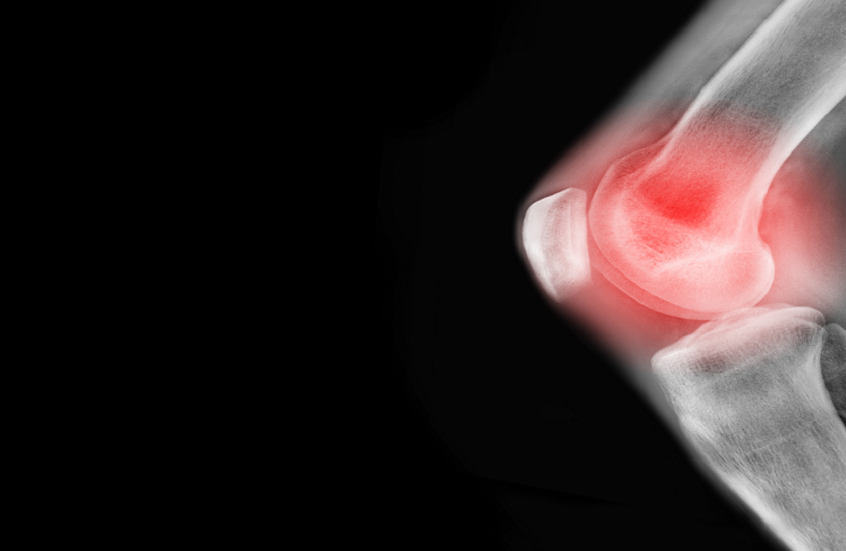

دراسة تؤكد فوائد تمارين اليوغا لعلاج آلام مفاصل الركبة

أظهرت دراسة أجراها باحثون أستراليون أن تمارين اليوغا لها أثر فعال في علاج آلام مفاصل الركبة.

وشملت الدراسة 117 شخصا أعمارهم تبدأ من 40 عاما، تم تشخيص إصابتهم بهشاشة العظام ويعانون من آلام في مفصل الركبة، وتم تقسيم المشاركين إلى مجموعتين: مجموعة طلب منها ممارسة تمارين القوة لاختبار فعالية هذه التمارين على تخفيف آلام مفاصلهم، والأخرى طلب منها ممارسة تمارين اليوغا.

استمرت الدراسة مدة 24 أسبوعا، وبعد 12 أسبوعا لاحظ الباحثون أن المشاركين من كلتا المجموعتين انخفضت لديهم معدلات آلام الركبة بشكل ملحوظ، وكان فرق الألم بين المشاركين من المجموعتين يعادل 1.1 فقط وفق مقياس VAS لشدة الألم، الأمر الذي أظهر أن تمارين اليوغا لا تقل أهمية عن تمارين القوة لعلاج مشكلات آلام مفصل الركبة.

وبعد مرور 24 أسبوعا من بدء الدراسة لاحظ الباحثون أن الأشخاص الذين مارسوا تمارين اليوغا ظهرت عليهم تحسنات أكبر من عدة نواح مقارنة من الذين تمارين القوة، إذ انخفضت معدلات ألم الركبة لديهم بشكل أكبر، كما تحسنت لديهم الوظائف الحركية، وقلت لديهم معدلات الاكتئاب، مما يشير إلى فوائد إضافية لليوغا على المدى الطويل مقارنة بتمارين القوة الرياضية التقليدية.

وأشارت القائمون على الدراسة إلى أن تمارين اليوغا وتمارين القوة كان لهما أثر واضح في علاج آلام الركبة، لكن اليوغا تفوقت من حيث تحسين نوعية الحياة لدى المرضى وتحسين حالتهم النفسية، لذا يمكن أن ينصح بتمارين اليوغا كعلاج مستقل أو علاج مكمل للذين يعانون من مشكلات آلام مفاصل الركبة.